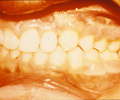

En el supuesto de que la fisura de la encía no se hubiera cerrado quirúrgicamente en el primer año de vida (gingivoperiostioplastia), se realizará entre los 7 y 11 años, previo tratamiento ortodóncico, y mediante la colocación de injertos óseos tomados de la cadera del propio niño.

| Encía fisurada | Injerto óseo en encía fisurada | Encía finalizada con el diente canino erupcionado a través del injerto óseo. |